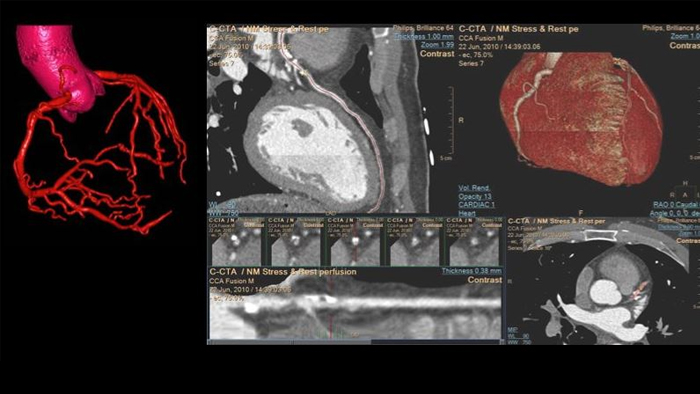

• Cardiac CT: Proven CT cardiac imaging capabilities, dose management tools, and exclusive clinical insights from detector-based Spectral CT.

Spotlight on: Cardiac CT (Spectral CT 7500)

See beyond routine cardiac imaging with the additional clinical information of Spectral CT for advanced cardiac applications. Learn how the Spectral CT 7500's "Always On" Spectral CT workflow helps you meet the needs of all your patients with zero compromises.